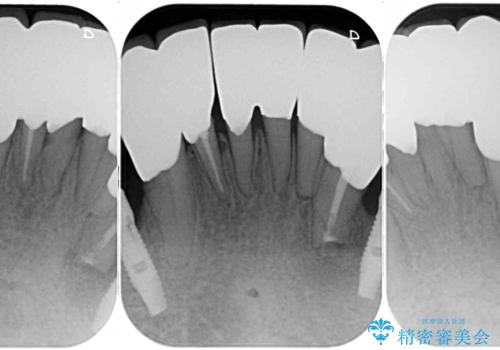

- どこで咬んでよいのか分からないとのことで来院された患者様です。

歯冠の崩壊した奥歯と、前歯の一部でした咬み合うことができず、入れ歯も試したものの、装着することができなかったようです。

全顎的にインプラント補綴を行うことも検討しましたが、費用面から、インプラントを土台とした入れ歯(インプラント・オーバーデンチャー)による補綴治療を行うこととしました。

入れ歯の固定源にはマグネットやロケーター、ボールアタッチメントなどがありますが、お住まいが遠方であることや、奥歯に力がかかりやすいことから、維持力が強く、メインテナンスが行いやすいロケーターを採用しました。